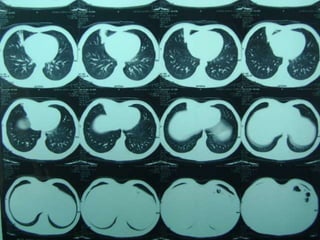

 LA TAC puede lograr

sospecha

 La Angio-TAC pulmonar

confirma al diagnóstico.

 Angiografía y el

Ecodoppler color, que

pueden mostrar la

irrigación sistémica del

secuestro.

OTRAS IMÁGENES  LATAC puede lograr sospecha  La Angio-TAC pulmonar confirma al diagnóstico.  Angiografía y el Ecodoppler color, que pueden mostrar la irrigación sistémica del secuestro.